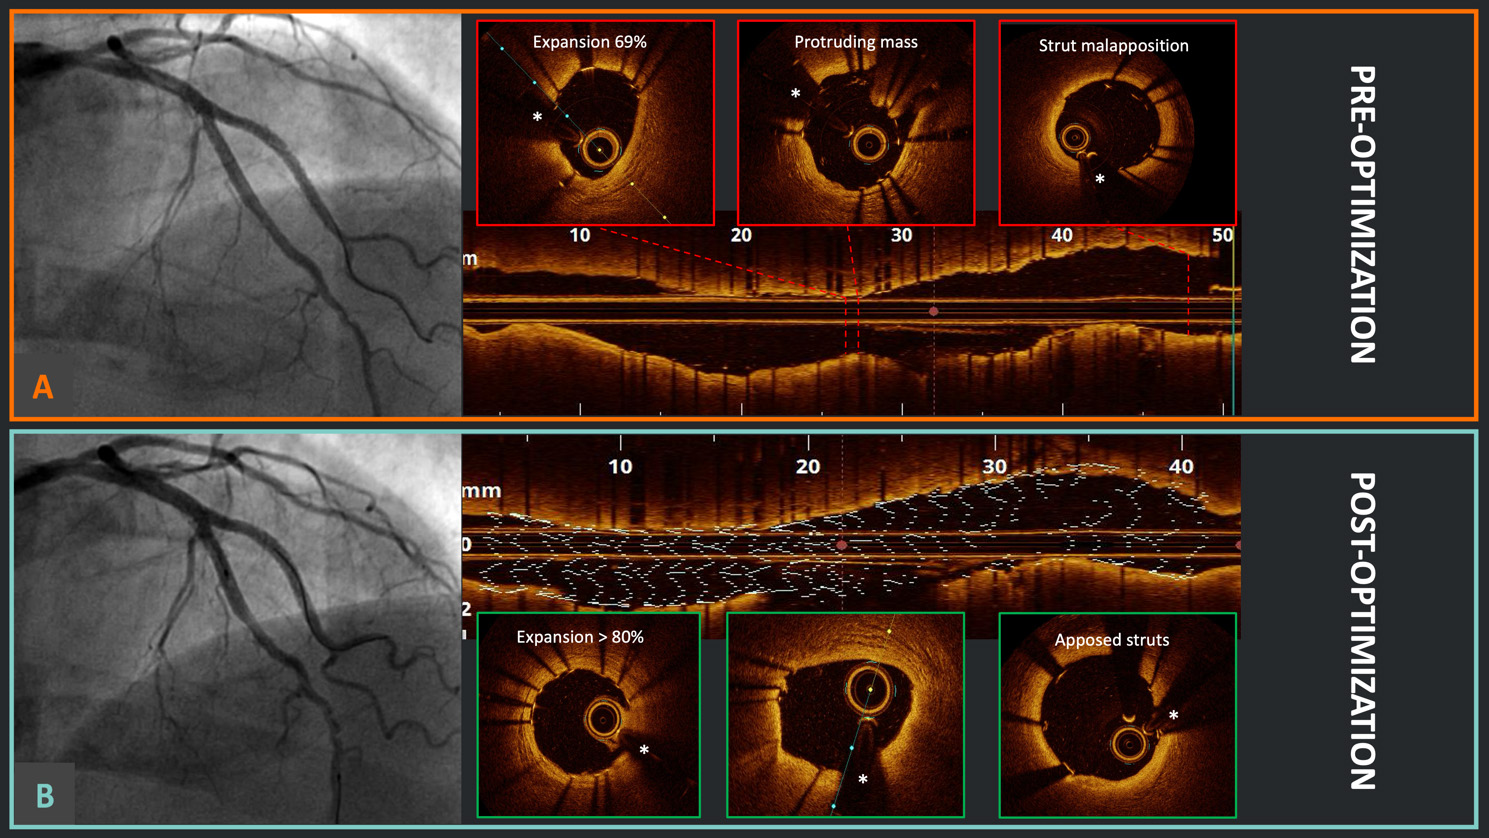

OCT can provide unique insights into the mechanisms underlying acute coronary syndromes (ACS) by accurately assessing vessel and lumen geometry and identifying the hallmarks of culprit lesions in ST- or non-ST elevation myocardial infarction, such as plaque disruption, intraluminal thrombus, and spotty calcifications [53]. Furthermore, OCT enables the differential diagnosis between plaque rupture and plaque erosion (an example of this is shown in Fig. 2). These two entities, despite their similar presentations, have distinct pathogeneses and treatments. In plaque rupture, luminal thrombosis is triggered by the contact of flowing blood with the highly thrombogenic necrotic core and with tissue factor, which is primarily derived from macrophages that are more prevalent in the case of fibrous cap disruption. In contrast, in the case of plaque erosion, local flow perturbations accompanied by upregulation of Toll-like receptor 2 and subsequent activation of platelets and endothelial denudation lead to occlusive thrombosis [54]. For plaque rupture, performing PCI to seal the prothrombotic cavity is the standard and largely validated approach [55]. In cases of confirmed plaque erosion, a conservative approach, combined with dual antiplatelet therapy, has been shown to be safe [56]. OCT is also critical for defining eruptive calcified nodules, a relatively rare but important cause of ACS with the highest incidence of MACEs, mainly driven by recurrent TLF and ACS at follow-up, with nodule re-protrusion even after stenting [57]. Finally, OCT can be an important tool in the diagnostic work-up of myocardial infarction with non-obstructive coronary arteries (MINOCA): after exclusion of atherosclerotic causes (plaque rupture, plaque erosion, calcified nodules), identification of non-atherosclerotic causes (spontaneous coronary artery dissection, epicardial spasm, thrombus embolization) can be critical for the tailoring of treatment [58], although more data are warranted in this setting.

Fig. 2. Diagnosis of plaque erosion. Example of angiographic acquisition of right coronary artery with suspected thrombus (“haziness”) in the context of acute coronary syndrome. The respective OCT cross-sectional frames (A–C) and longitudinal reconstruction (D), evidencing (B) red thrombus with typical protrusions in the lumen with high back-scattering and high signal attenuation (white arrow) and healthy vessel walls proximally (A) and distally (C) to the culprit segment. OCT, optical coherence tomography. *Wire artifact.